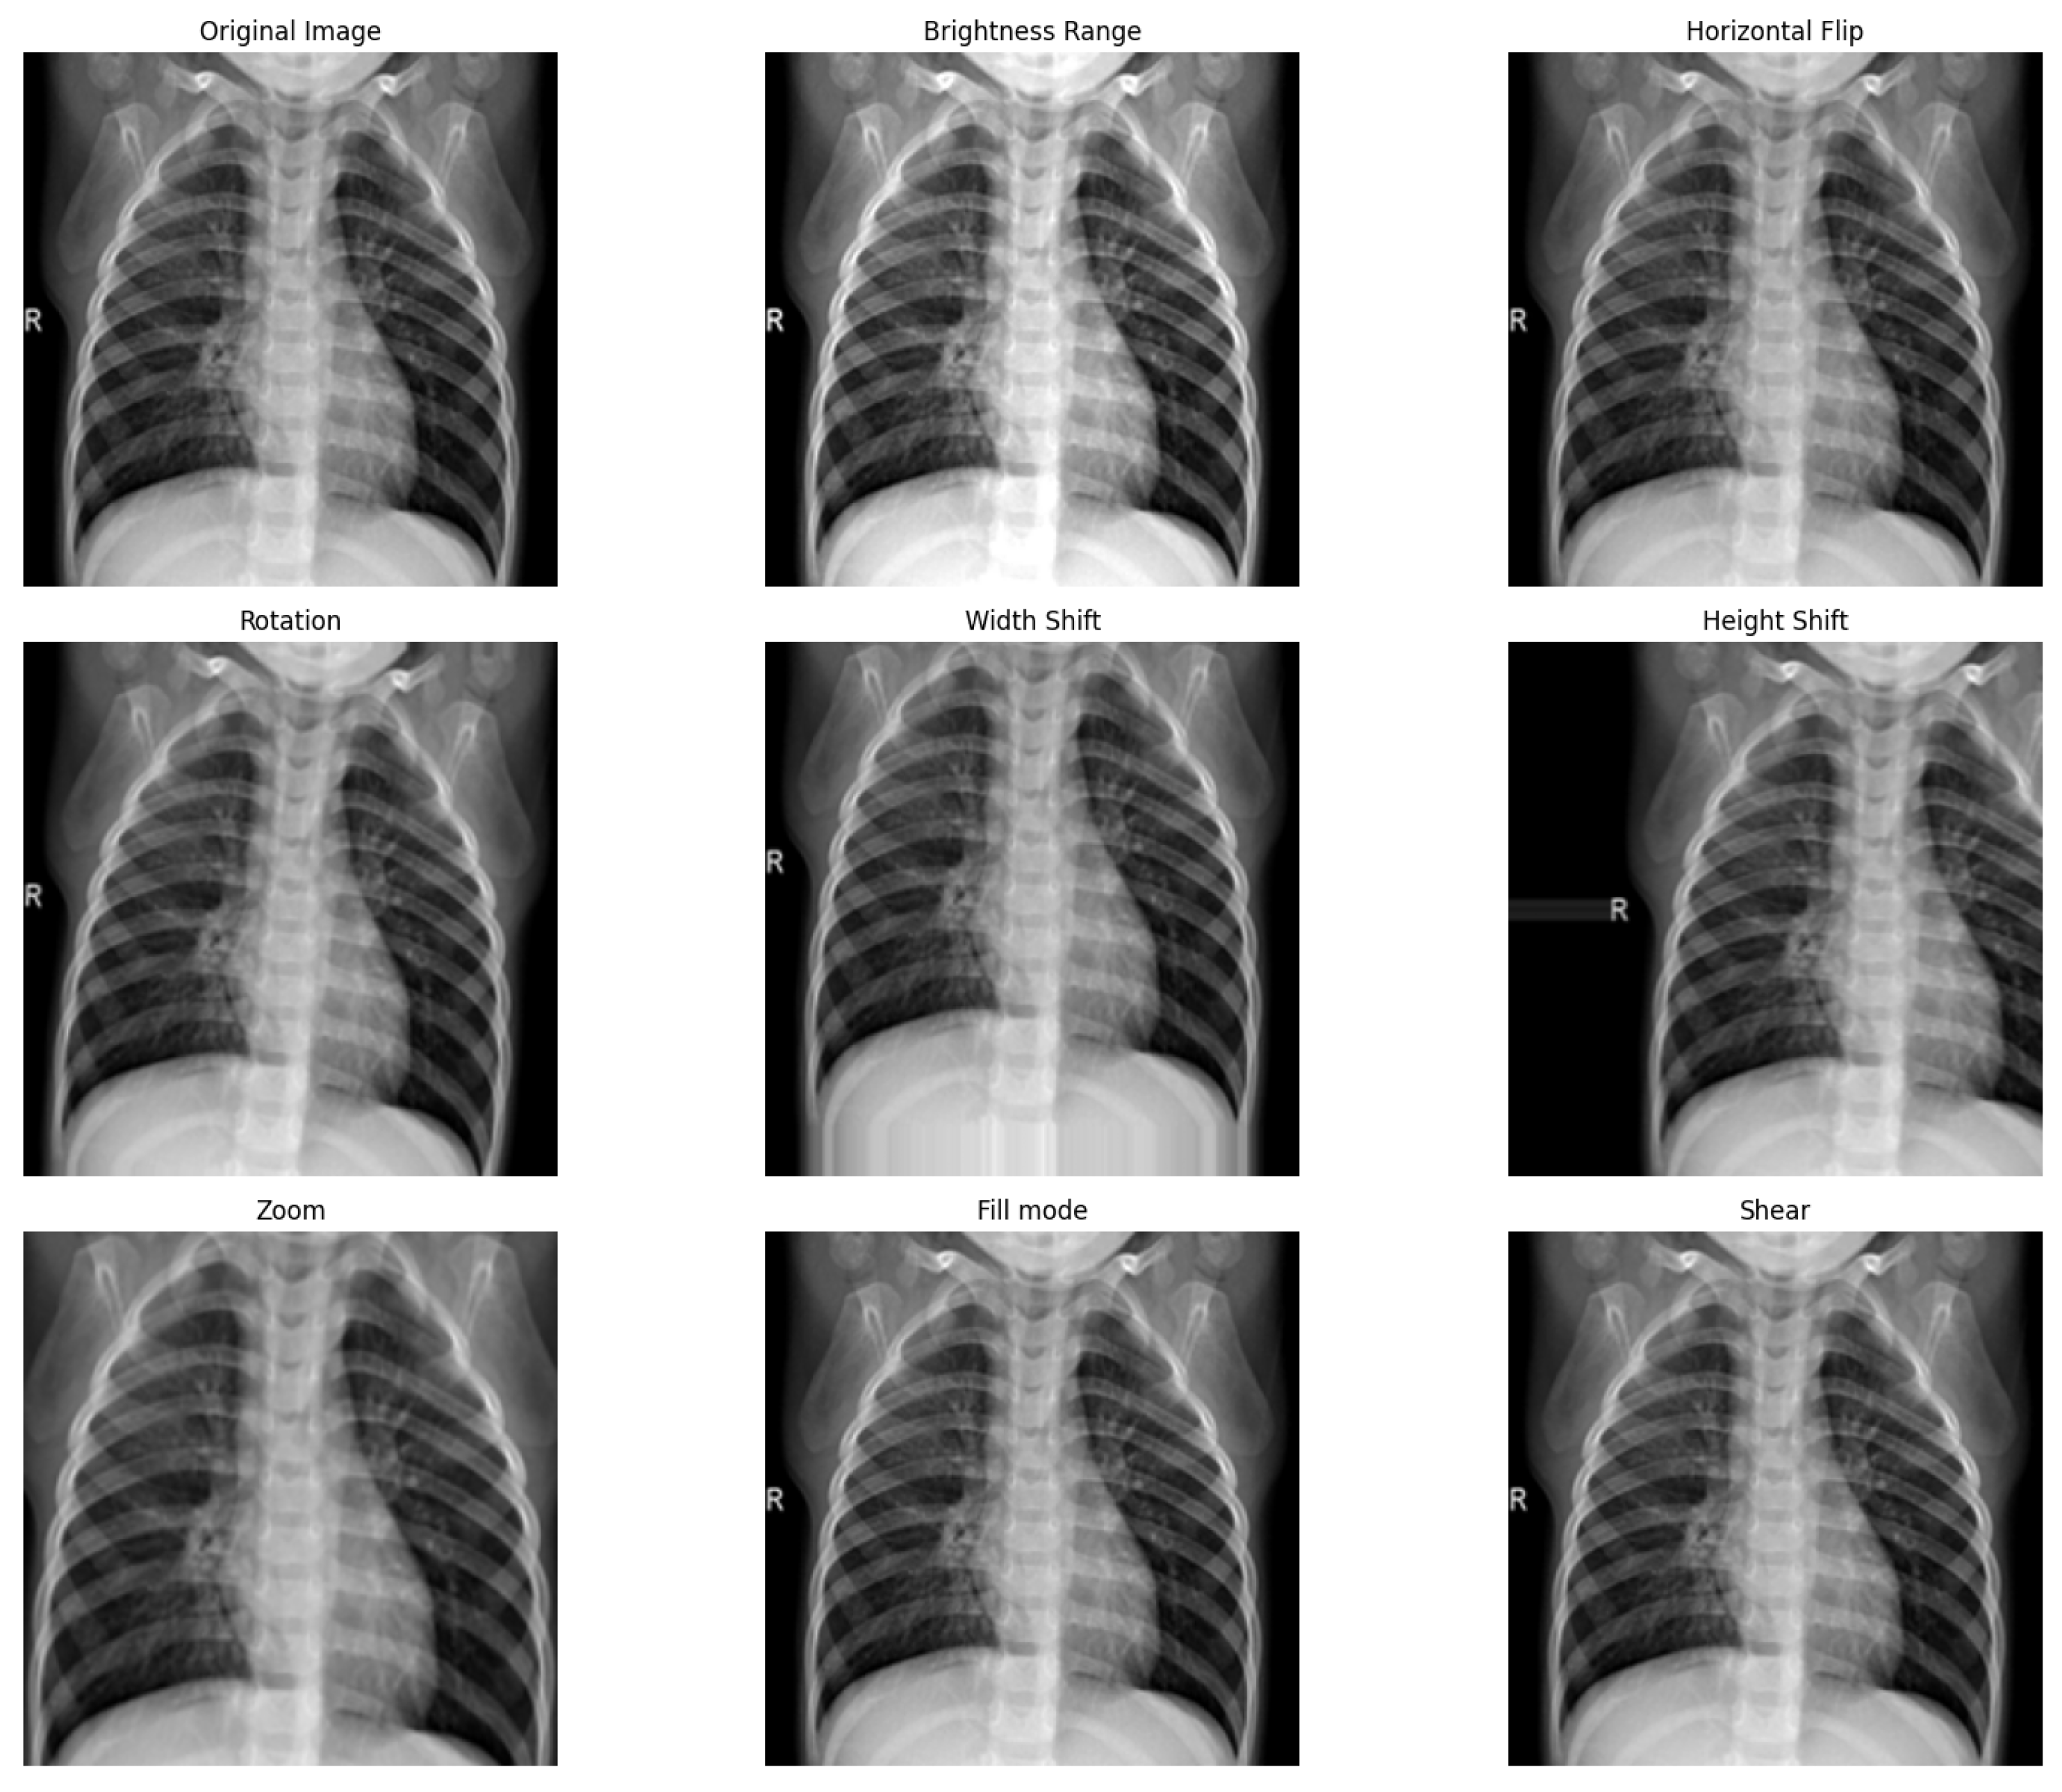

In our study, we adopted image augmentation strategies [35,36] to address the challenges arising from the limited volume of images in our training collection and improve the training procedure’s effectiveness. These augmentation strategies [37,38] involve different modifications that enlarge the training collection and introduce a broad spectrum of image scales and orientations. Such variety was crucial as it helped to prevent the model from overfitting to the specific characteristics of the training images, thus enhancing the model’s ability to generalize effectively to new, unseen collections.

Specifically, we implemented a comprehensive suite of data augmentation techniques across all categories of lung conditions, with the exception of normal lung conditions, to refine the rate of our training collection as outlined in Table 2. Consequently, a separate category within the training collection now included 6570 images, such as normal lung infections. These augmentation strategies were essential for bolstering the variety and robustness of our training collection. They contained modifications such as random rotations, height and width shifts, adjustments in brightness, zooming, shearing transformations, horizontal flipping, and alterations in fill mode. These methods were instrumental in creating a more versatile and representative training collection, ensuring that the resulting model was accurate and robust across various imaging scenarios.

The parameters outlined in Table 2 were chosen based on empirical testing and established practices in the field of DL for medical imaging. Our goal was to create robust augmentation techniques to effectively simulate the variability encountered in real-world clinical settings, thereby enhancing the model’s ability to generalize across diverse imaging scenarios. The brightness, rotation, width shift, height shift, and zoom ranges were determined through experimentation to select values that introduced sufficient variability without distorting the medical relevance of the images. The fractional values, such as the height shift and shear parameters, were selected as fixed values after preliminary experiments, which produced the best results regarding model accuracy and robustness. A spread in the distribution was not applied because the chosen values effectively mimicked the shifts and distortions seen in clinical X-rays without introducing unrealistic alterations.

Figure 3 illustrates instances of data augmentation strategies implemented on the training dataset. Each technique introduced distinct modifications to the images, compelling the model to focus on learning the critical features of the anatomical structures despite these variations. This approach was crucial for ensuring that the model’s performance remained robust, enabling it to interpret images across various imaging conditions accurately. By training the model to recognize essential features under varied conditions, we enhanced its ability to generalize from the training data to new data, thus improving its diagnostic reliability in practical settings.

Figure 3.

Example of data augmentation strategies applied to viral pneumonia.